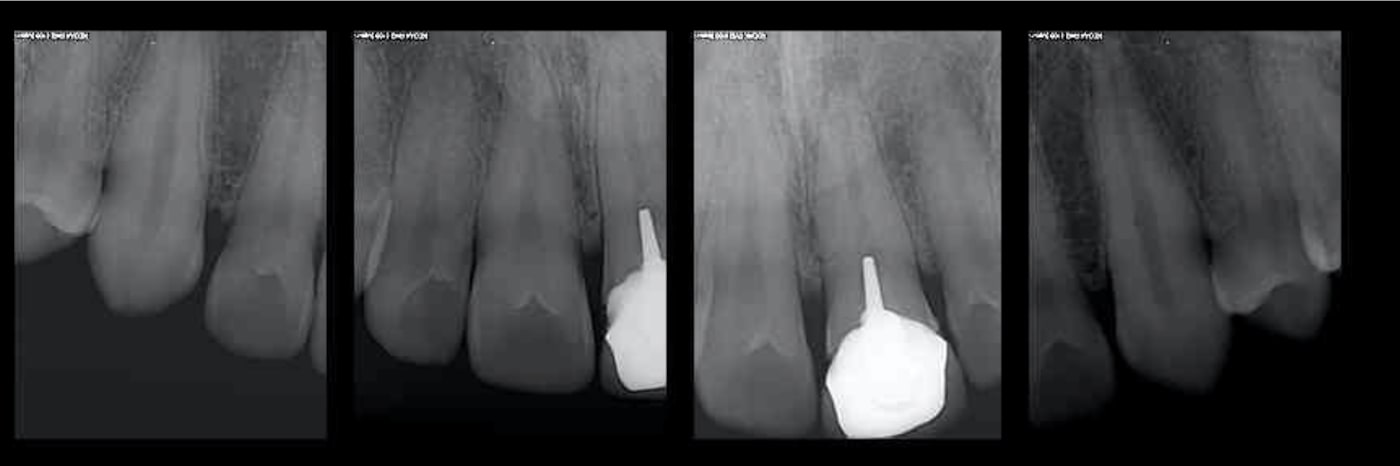

Ca c'est encore plus vieux (ca te fait en plus l'économie d'une endo pour la sécu) mais ca marche aussi. Comme quoi ....-)

G3hnxytnkxxl07jk4xqttga0fbry - Eugenol